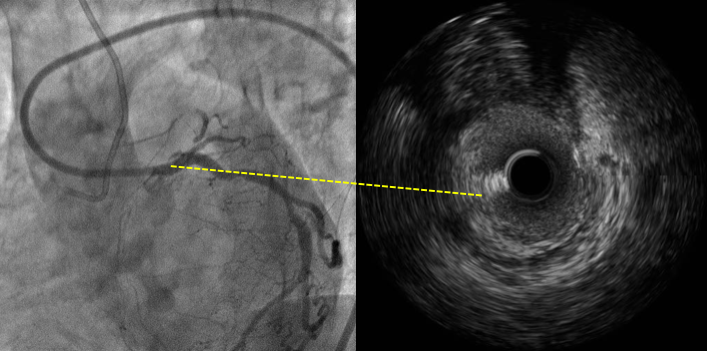

结合IVUS图像确认穿刺点及穿刺方向

Discrepancy

MC+ pilot 150, crossed